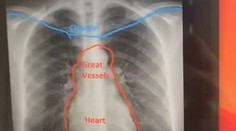

USA Tínedžerku (19) dlhšie trápil kašeľ. Následné röntgenové vyšetrenie odhalilo nečakanú anomáliu Róbert Ďurkáč 21. 7. 2021